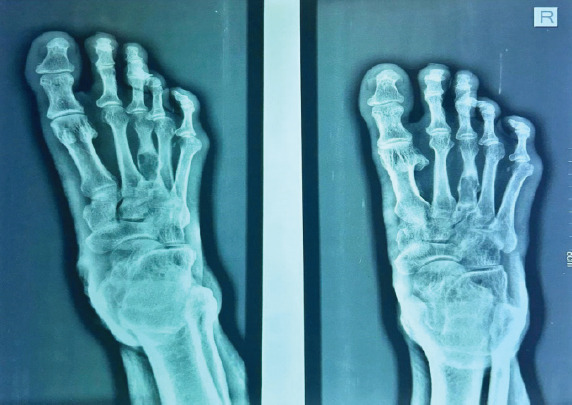

Case report: We present a case of a 65-year-old male farmer who presented with swelling and persistent pain in the right foot, particularly over the third toe. The patient had a history of trivial trauma and previous incision and drainage for a foot swelling. Radiographic and magnetic resonance imaging findings indicated a well-defined lytic lesion with cortical thinning and breach over the third metatarsal, raising suspicion for tuberculous osteomyelitis. Surgical exploration revealed an encapsulated cyst filled with cheesy material. No sequestrated bone or osteomyelitis was found.